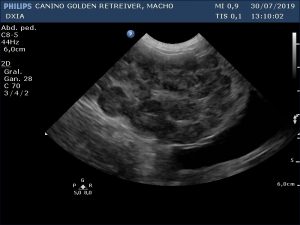

Ecografía Abdominal DXIA Scott

Bazo. No esplenomegalia. Parénquima esplénico homogéneo y normoecoico.

Lóbulo hepático.

Parénquima hepático homogéneo en lóbulos caudal a la vesícula biliar y lóbulo derecho próximo al estómago, pero en el resto del hígado se observa hepatomegalia (al presentar bordes hepáticos redondeados) junto con patrón marcado nodular que le da heterogenicidad. Se realiza PAF ecoguiada para su posterior análisis anatomopatológico, pero si no es suficiente la muestra se requerirá la realización de biopsia.

Vesícula biliar con pared fina e hiperecogénica. No presencia de barro biliar.

Conclusión del estudio ecográfico abdominal

Sólo se observa alteración en parénquima hepático resto de vísceras abdominales incluidas los ganglios eran normales. Debida a la poca carga parasitaria que presenta el paciente (no se han detectado Filarias adultas a nivel cardíaco) no se considera, en principio, entre los diferenciales que dicha alteración hepática sea secundarias a Filarias erráticas. Por lo que se decide realizar PAF en ese mismo estudio, siempre con consentimiento de su propietario.

Primera Imagen Hígado DXIA Scott

Primera Imagen Hígado donde se obtuvo la PAF